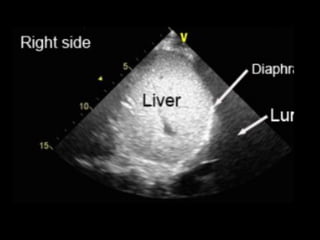

SUBCOSTAL